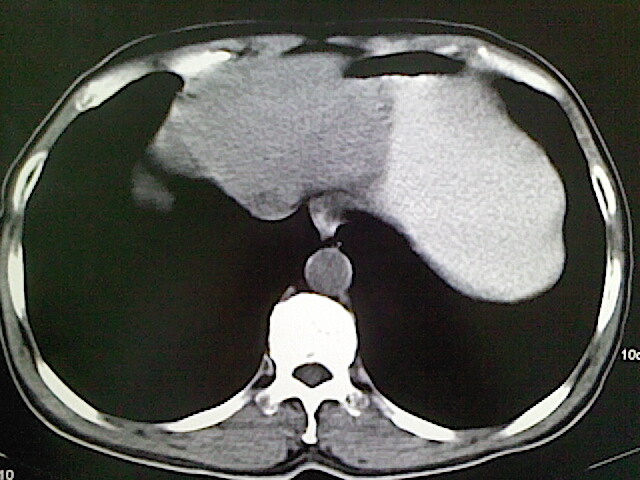

标题: CT18630:男,54岁,乙肝,大家看怎么样? [打印本页]

男,54岁,乙肝,大家看怎么样?

肝脏的要有增强敢说话

未见明确异常;建议必要时行ct增强扫描检查。